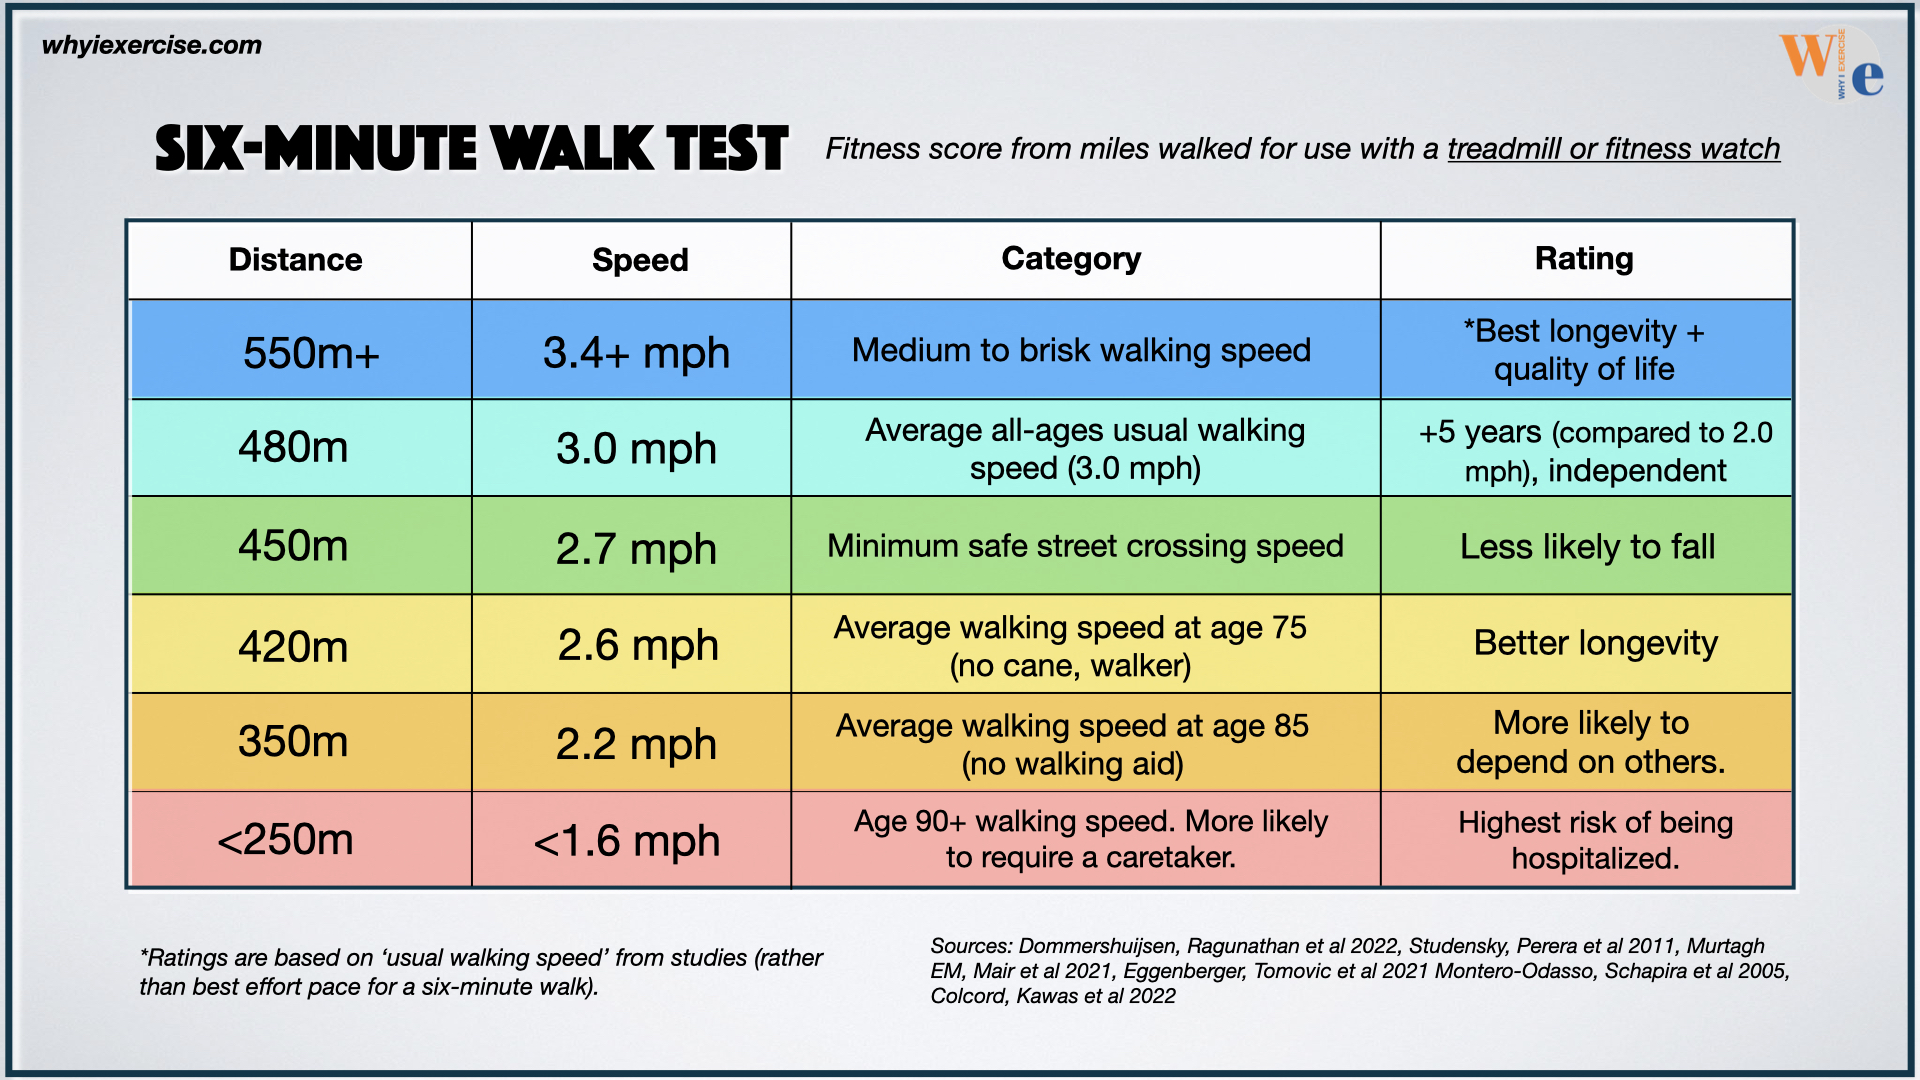

Brisk Walking